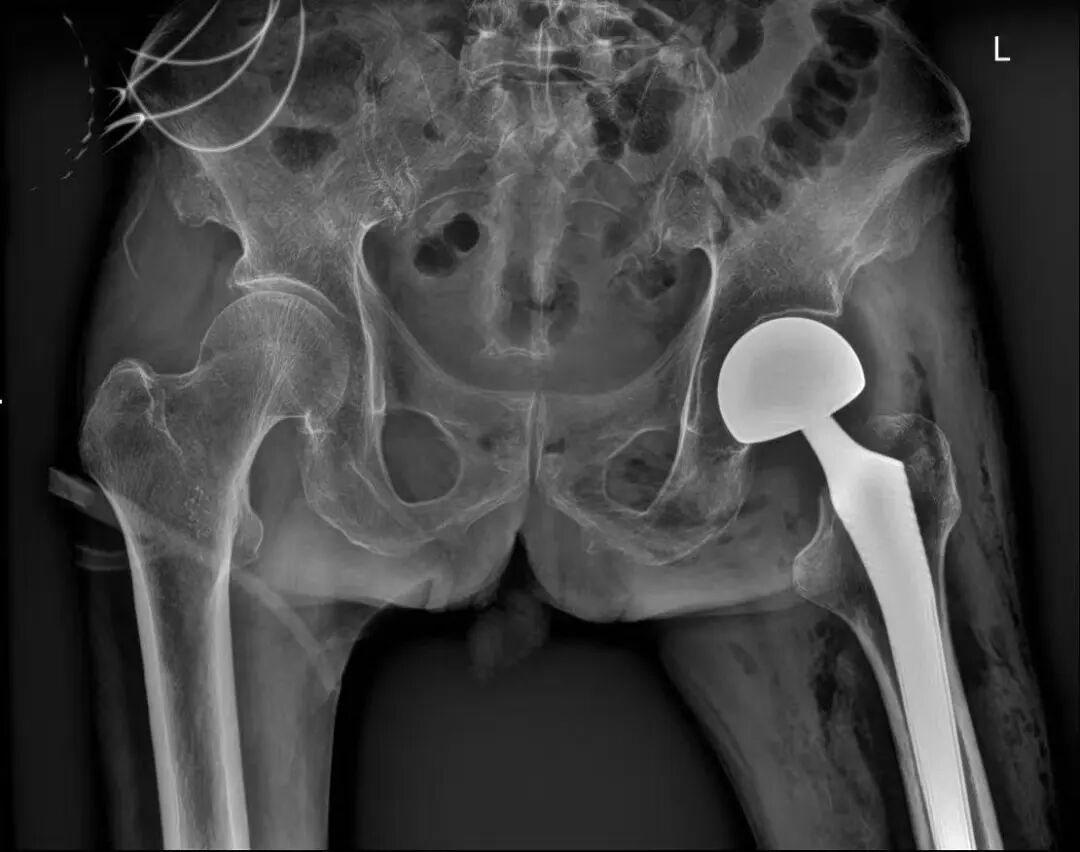

【医疗动态】突破高龄“禁区”!我院成功为93岁老人实施“微创DAA股骨头置换术”

今年93岁的陈爷爷不慎摔倒后,被紧急送往我院就诊,经影像学检查确诊为“左侧股骨颈骨折”。对于老年人而言,股骨颈骨折素有“人生最后一次骨折”之称,保守治疗需长期卧床,不仅会大幅降低生活质量,更易引发肺部感染、深静脉血栓、褥疮等致命并发症,危及生命。但93岁的超高龄的患者,伴有心肺功能减退、严重骨质疏松等问题,麻醉耐受度极差,手术风险堪比“闯雷区”。

面对患者及家属强烈的康复意愿,我院骨科主任马骏第一时间组织多学科诊疗(MDT),联合相关科室全面评估患者身体状况,反复研讨优化手术方案。“传统髋关节置换手术创伤大、出血多,超高龄患者难以耐受。”马骏主任介绍,为最大程度减少创伤,团队决定采用国际领先的DAA微创技术,该技术利用肌肉间的“天然缝隙”进入关节,不切断任何肌肉和肌腱,具有创伤小、恢复快、脱位风险低的显著优势。

在上海市第一人民医院驻酒专家余壮教授的指导下,手术团队为患者实施蛛网膜下腔阻滞麻醉,全程精准操作、密切监测,仅用不到40分钟便顺利完成股骨头置换,术中患者生命体征平稳,出血量不足100毫升。术后,护理团队量身定制康复计划,遵循加速康复理念,术后6小时指导老人进行踝泵运动,术后第一天协助老人坐起进食,术后第二天老人便可借助助行器稳稳站立行走。